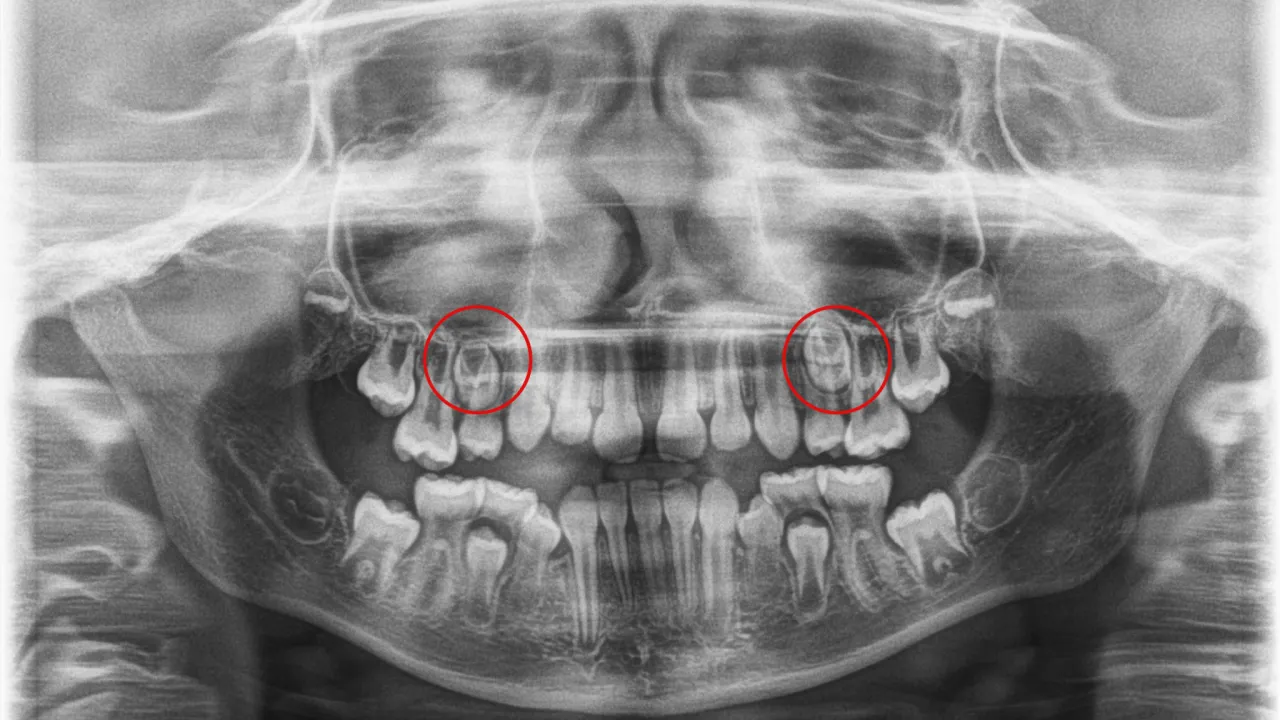

Ząb stały rośnie za mlecznym: czy "zęby rekina" to powód do paniki?

Zjawisko "zębów rekina", czyli sytuacja, w której ząb stały wyrzyna się za zębem mlecznym, zanim ten zdąży wypaść, jest dość powszechne i często budzi niepokój rodziców. Najczęściej dotyczy to dolnych siekaczy. Chcę Państwa uspokoić w większości przypadków nie ma powodu do paniki. Mleczak zazwyczaj wypada samoistnie w ciągu kilku tygodni, a język dziecka naturalnie "wypycha" ząb stały na właściwe miejsce. Jednak jeśli mleczak nie wypadnie po kilku tygodniach od pojawienia się zęba stałego, lub jeśli ząb stały wyrzyna się w bardzo nieprawidłowej pozycji, warto skonsultować się z dentystą. Czasami konieczne jest usunięcie przetrwałego zęba mlecznego.

Dlaczego ząb mleczny nie wypada, mimo że wyrósł już stały?

Problem przetrwałego zęba mlecznego, czyli sytuacji, gdy ząb mleczny nie wypada, mimo że nadszedł na to czas, a ząb stały już się wyrżnął lub powinien się wyrżnąć, jest poważniejszy. Przyczyny mogą być różne:

- Brak zawiązka zęba stałego: Czasami pod zębem mlecznym po prostu nie ma zęba stałego, który by go wypchnął.

- Nieprawidłowe położenie zawiązka zęba stałego: Ząb stały może rosnąć w niewłaściwym kierunku, nie naciskając na korzeń mleczaka.

- Ankyloza: Ząb mleczny może być zrośnięty z kością, co uniemożliwia jego naturalne wypadnięcie.

W takich przypadkach konieczna jest diagnostyka, najczęściej w postaci zdjęcia rentgenowskiego (RTG), aby ocenić sytuację. Często niezbędna jest również konsultacja ortodontyczna, ponieważ przetrwały ząb mleczny może prowadzić do poważnych wad zgryzu i problemów z ustawieniem zębów stałych.